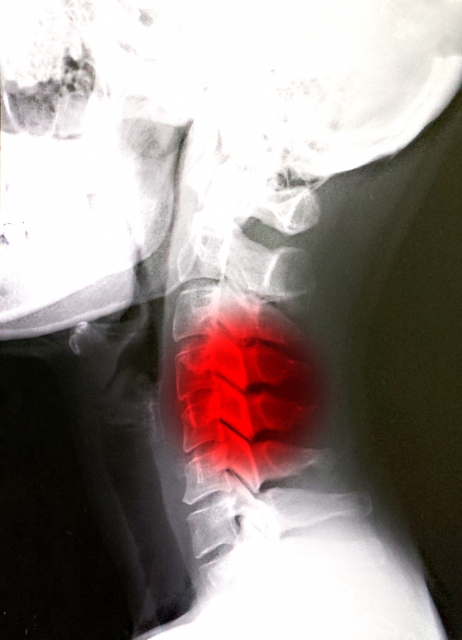

【頚椎椎間板ヘルニア】

頚椎椎間板ヘルニアは、首の骨(頚椎)の間にある椎間板が飛び出し、神経を圧迫することで痛みやしびれが出る状態です。